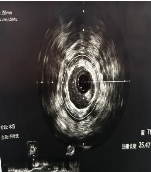

这次接受手术的患者,因反复胸闷、胸痛入院。经冠脉造影和血管内超声检查,确诊为左主干—前降支全程弥漫性病变。具体来看:

◆左主干体尾部狭窄约 50%,血管内最小管腔面积 3.35mm^2(正常应大于6mm^2)

◆前降支中段狭窄最重达 90%

(术前)